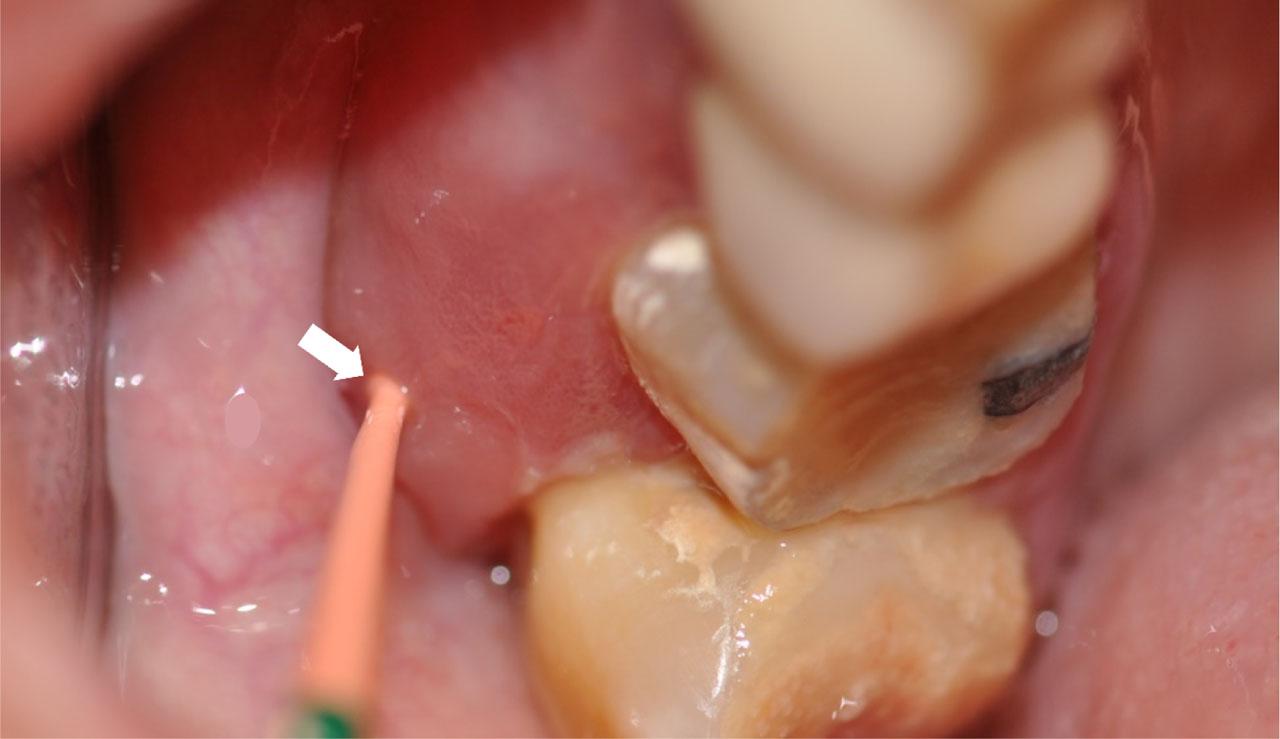

Figure 2:

Osteonecrosis on the maxilla was diagnosed after probing necrotic bone through a fistula (arrow). A plastic material (gutaperka) was inserted into the fistula to better disclose the fistula. Patient presented with pain and swelling.